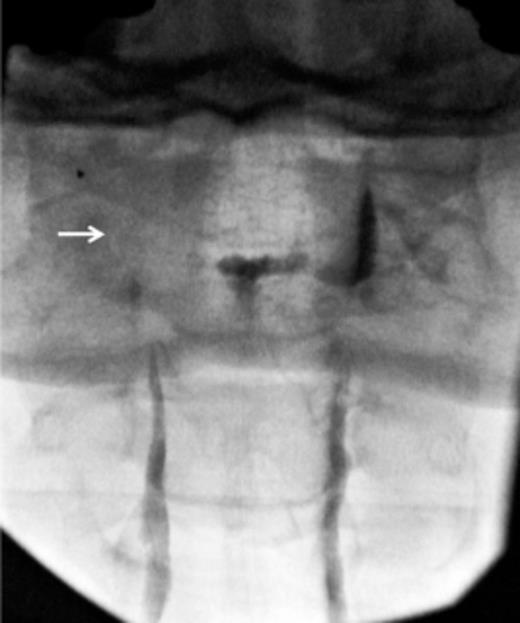

The patient developed cauda equina syndrome after six epidural blood patches. The clinical diagnosis was confirmed by magnetic resonance imaging and the intradural haematoma was evacuated surgically. The patient made a complete recovery. Conclusions Epidural blood patch is not without complications. Transient backache and/or radiculopathy may occur in up to one-third of patients receiving a blood patch.

If signs and symptoms continue or worsen, a spinal subarachnoid and/or subdural haematoma should be suspected and neurosurgical opinion sought. The technique used to identify the epidural space is important in preventing subdural injection of blood. The needle should be withdrawn after durai puncture and the epidural space identified at a different level. Blood patches may carry a higher risk of serious complications after multiple epidural phenol injections because of fibrosis and obliteration of the epidural space. Magnetic resonance scans reliably demonstrate the extent of the pathology. If diagnosed and treated before irreversible changes occur, spinal intradural haematoma can result in complete recovery.